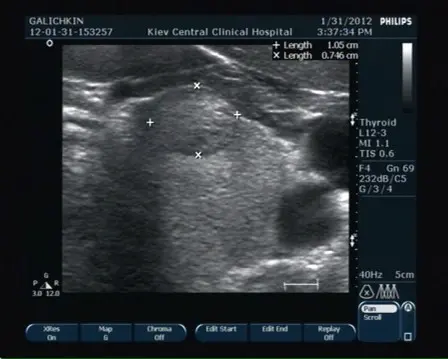

УЗД щитовидної залози. Один і той же пацієнт, дослідження щитовидної залози з інтервалом в 3 роки, збільшення вузла з розмірів 11х7х10 мм до 26х17х19 мм. Освіта визнано доброякісним. (Різниця в кольорі знімків – розрив апарати)